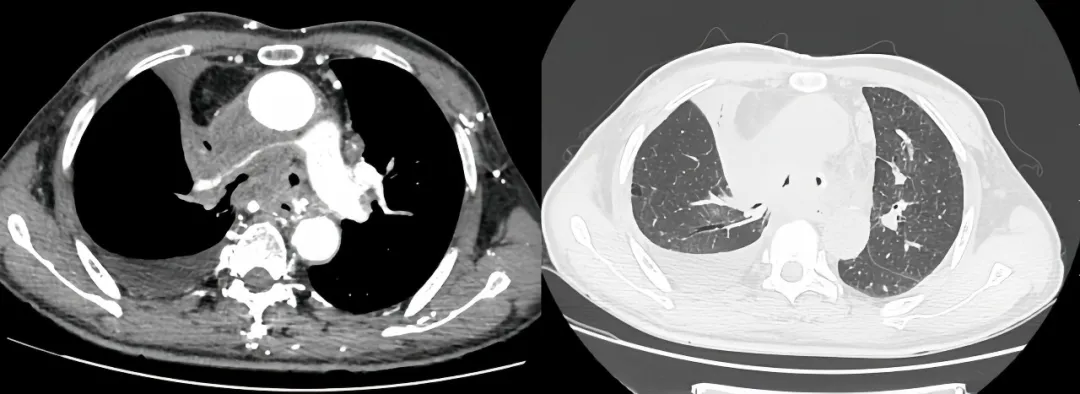

术前受压变窄的右肺动脉和中央气道

同期置入支架后狭窄明显改善